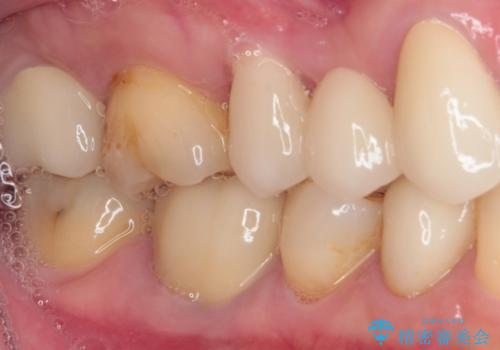

- 他院で矯正治療を終えたものの、むし歯や欠損部の治療が進められないとのことで来院された患者様です。

欠損部や、銀歯やむし歯の大きな歯はセラミッククラウンやブリッジに、小さいむし歯はセラミックインレーにて治療を行うこととしました。